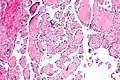

Intravascular papillary endothelial hyperplasia is a rare, benign tumor. It may mimic an angiosarcoma, with lesions that are red or purplish 5-mm to 5-cm papules and deep nodules on the head, neck, or upper extremities.[1][2]: 592

Histopathology Images